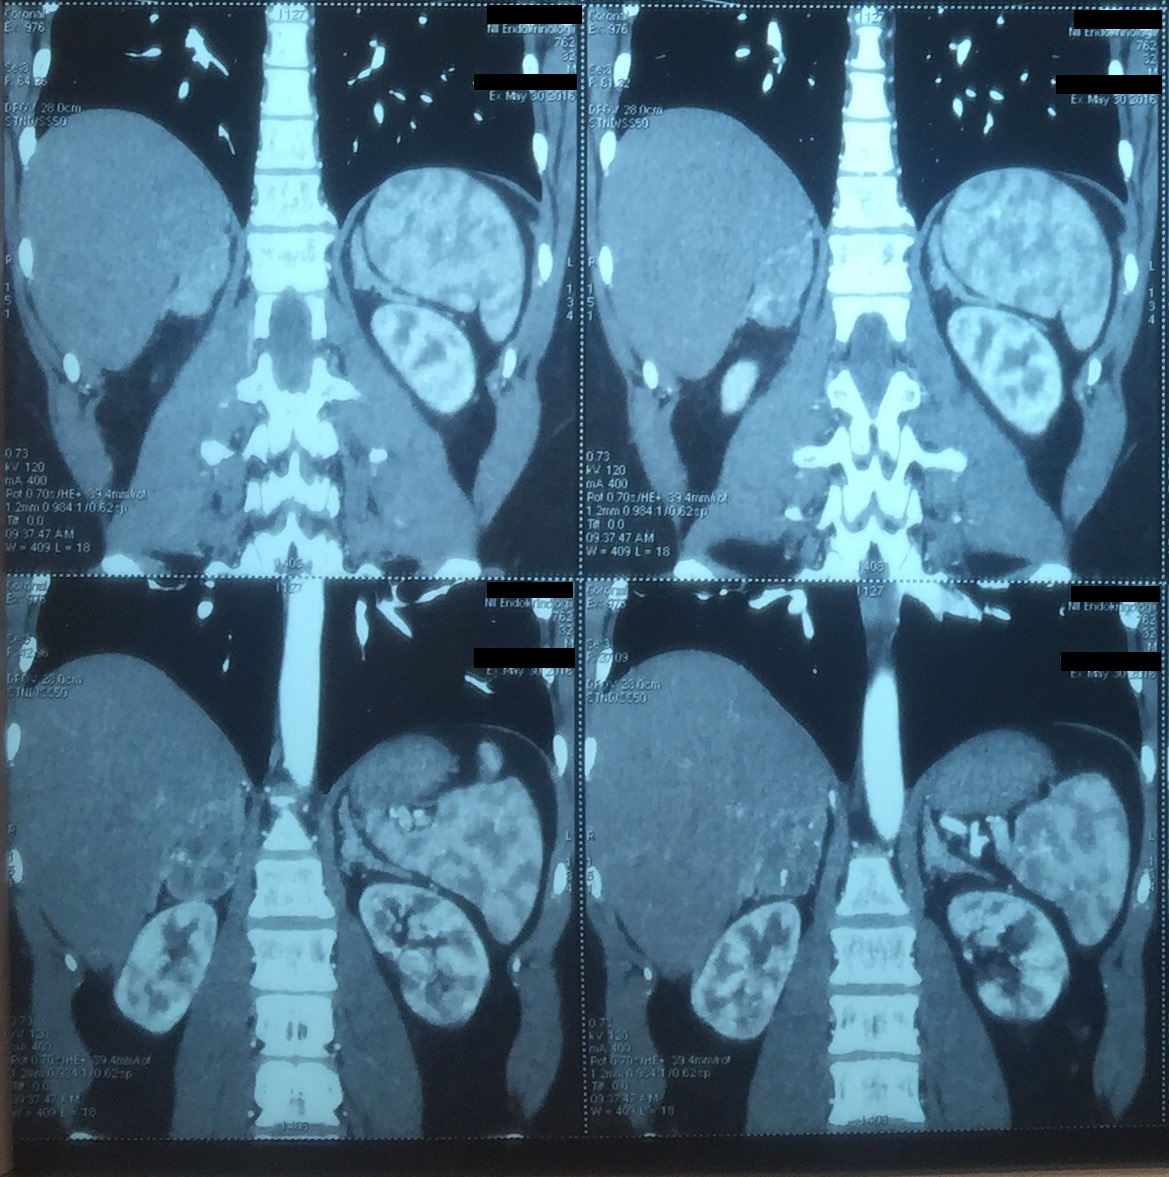

При МРТ головного мозга данных за патологию, в том числе гипофиза, не получено. При МСКТ брюшной полости у пациента была выявлена аденома правого надпочечника размером 48×35×43 мм на фоне двустороннего утолщения надпочечников (рис. 2).

Рис. 2. МСКТ брюшной полости пациента О.

Определяется аденома правого надпочечника, двустороннее утолщение надпочечников.

Длительная декомпенсация ВДКН, сопровождающаяся значительным повышением уровня АКТГ, объясняет развитие двусторонней гиперплазии надпочечников и аденомы правого надпочечника. В связи с высоким уровнем андрогенов адреналового происхождения у пациента развился гипогонадотропный гипогонадизм, сопровождающийся гипоплазией яичек, азооспермией.

Одним из частых осложнений при поздней диагностике ВДКН или его длительной недостаточной компенсации являются вторичные образования в надпочечниках [9, 10], которые были выявлены и у нашего пациента. Так как появление аденом связано с длительной массивной гиперстимуляцией надпочечников АКТГ, то в большинстве случаев они подвергаются регрессии на фоне адекватной стероидной терапии. Хирургическое лечение применяется в исключительных случаях, при появлении признаков функциональной автономии образования. В нашем случае значительное снижение АА и 17-ОПГ на фоне терапии указывало на хорошую чувствительность аденом к стероидам.